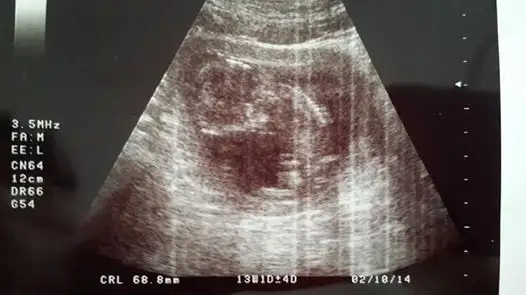

ya kızlar benim iki hafata önceki ultrasonum var belli midir? dr erkek muhtemelen dedi ama kesin demedi. yeni ultrasonu ekleyemedim bir türlü ışık patlaması oluyor. çocuğun kafası kocaman görüyodu korktum ya siiznkilerde de öyle oldu mu? kötü bişey olsa dr söylerdi dimi? ya da ultrasn eski diye mi öyle çıktı?

Eki Görüntüle 1016535